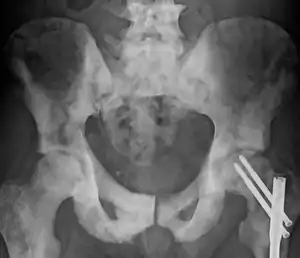

Osteosclerose é o aumento anormal da densidade ósseo,[1] devido à substituição de osso trabecular (saudável) por osso compacto, mais pesado, menos maleável e atrofiando a medula óssea. Pode ser detectada por uma radiografia simples por uma marcada opacidade. É um sintoma de muitas doenças diferentes, algumas hereditárias e outras adquiridas.